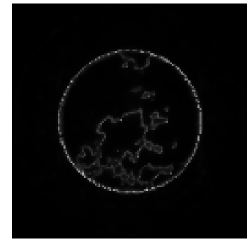

The noise model was assumed to be invariant under the two hypotheses. This assumption is particularly reasonable in our case in light of the fact that the signal of interest is small, with size on the order of only a few detector bins. An example of a pair of images used in the human observer study is presented in the top row of Fig. 3.

The reconstruction algorithm used was the FBP algorithm discussed in section 2. Projection data for the reference case was acquired over a full rotation at 1024 evenly spaced angles with 256 detector elements. The reconstruction was performed onto a pixel image grid with pixels roughly twice the size of a single detector element. The images were then cropped to a central pixel ROI, which was then displayed at magnification. Black and white lines were then superimposed on the image in order to aid the observers in localizing the signal at the center of the ROI. The reference images for the human and model observer study were reconstructed without regularization, i.e. with only the ramp kernel used for filtration. The ratio of the source-to-detector distance to the source’s radius of rotation was . The reference reconstructed signal is shown on the top left of Fig. 1. Visible artifacts in the reconstructed signal are a result of the discretization in the sinogram and image domains and the small size of the signal. This small signal size is desirable in this case because we can then expect greater variability in observer performance with respect to the reconstruction algorithm with the given noise model. The corresponding Hotelling template is pictured on the top right of Fig. 1.

As mentioned in Section 2, regularization can be performed in fan-beam FBP by applying a multiplicative apodization window to the ramp kernel in the Fourier domain. A case of heavy regularization is considered here, wherein a Hanning window with cutoff frequency equal to of the Nyquist frequency is used. For this case, we expect a drop in HO SNR relative to the reference (unmodified ramp kernel) case since this multiplicative window will place high-frequency components of the weighted projection data in the null-space of the reconstruction operator. The mean reconstructed signal and Hotelling template for the regularized study are shown in the middle row of Fig. 1.

Next, we considered the case of reconstruction onto pixels which are a factor of four larger than in the reference case, i.e. approximately eight detector bin widths square. Here, the expected loss in HO SNR arises from the fact that the reconstruction matrix has a more significant null-space due to the lower number of output image pixels relative to the number of input data elements. In other words, the matrix is now farther from being square, transforming an -element data vector to an -element image array where . The mean reconstructed signal and Hotelling template for the study involving larger pixels is shown in the bottom row of Fig. 1. Example pairs of images used in the regularization and large pixel studies are shown in the middle and bottom of Fig. 3.